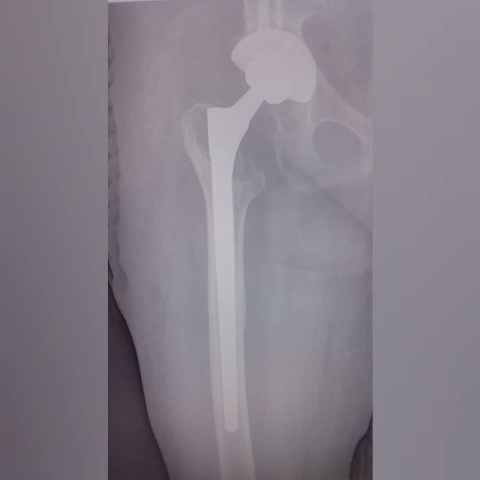

В красноярской БСМП им. Н.С. Карповича теперь делают операции, относящиеся к экспертному классу. Травматологи больницы теперь оказывают помощь пациентам, нуждающимся в ревизионном эндопротезировании суставов. Об этом рассказали в Минздраве края.

Речь идёт о полной или частичной замене ранее установленного эндопротеза. В данном виде операции нуждаются пациенты, которым ранее установили искусственный сустав, но по какой-то причине возникли осложнения, либо потребовалась его замена. По статистике таких пациентов немного — всего 1-2%, но в каждом случае требуется высокотехнологичная медицинская помощь.

Фото: kraszdrav.ru